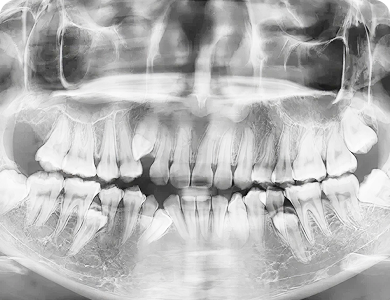

Niet doorgebroken gebitselementen

Het kan gebeuren dat een tand niet vanzelf doorbreekt en in het kaakbot blijft steken. Dit komt het meest voor bij de hoektanden in de bovenkaak, maar kan ook bij andere tanden gebeuren.